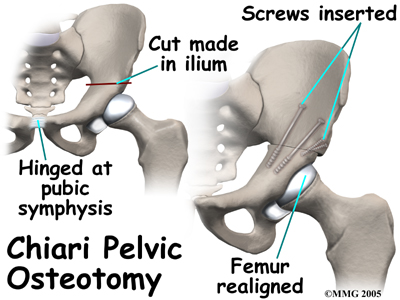

Surgical treatment for containment usually consists of procedures that realign the femur (thighbone), the acetabulum (hip socket), or both.

Realignment of the femur is called a femoral osteotomy. This procedure changes the angle of the femoral neck so that the femoral head points more towards the socket. To perform this procedure, an incision is made in the side of the thigh. The bone of the femur is cut and realigned in a new position. A large metal plate and screws are then inserted to hold the bones in the new position until the bone has healed. The plate and screws may need to be removed once the bone has healed.

Realignment of the acetabulum is called a pelvic osteotomy. This procedure changes the angle of the acetabulum (socket) so that it better covers, or contains, the femoral head. To perform this procedure, an incision is made in the side of the buttock. The bone of the pelvis is cut and realigned in a new position. Large metal pins or screws are then inserted to hold the bones in the new position until the bone has healed. The pins usually must be removed once the bone has healed.